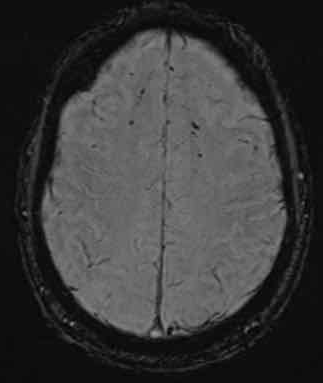

弥漫性轴索损伤(DAI)MRI表现

- 累及皮质下区、胼胝体、右侧丘脑和壳核、脑干、小脑脚和右侧小脑半球。

- 轻度全球萎缩。

MRI可准确诊断DAI,包括T2*GRE或SWI。

DAI在颅脑损伤患者MRI上的存在,更有可能导致不良的功能结局。